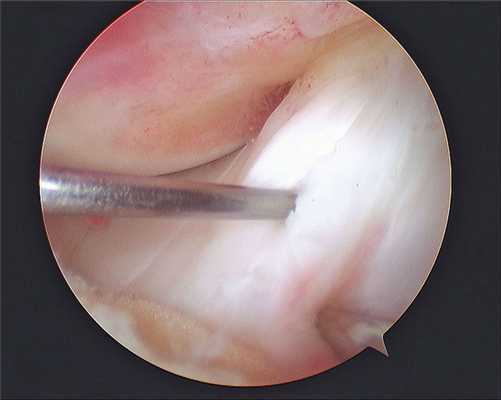

Все артроскопические вмешательства выполняют под визуальным контролем. Для визуализации внутрисуставных структур в суставную полость вводят артроскоп, который представляет собой жестко соединенные между собой трубку и окулярный оголовок. Изображение из артроскопа выводится на экран в операционной, что позволяет хирургу контролировать свои действия, а пациенту — наблюдать за ходом хирургического вмешательства.

Хирург делает несколько небольших разрезов на колене. В них закачивают стерильную соленую воду или физиологический раствор для расширения. В сустав вводят артроскоп с встроенной камерой. Изображение с нее транслируется на монитор в операционной. Специалист осматривает сустав, завороты и складки, обнаруживает проблему, затем, если клиническая картина позволяет, вставляет в разрезы небольшие инструменты и исправляет проблему (например, иссекает поврежденные участки мениска).

В целях высокоинформативной диагностики специалист через микропортал вводит рабочую трубку устройства внутрь сустава, в которую вмонтированы система ультрасильных линз, мощный световой источник и видеозаписывающая цифровая техника. Все структуры, что «видит» артроскоп, визуализируются на экране в «живом» виде, причем изображение поступает в многократно увеличенном формате. Врач может найти точное расположение травмы или дегенеративных изменений, установить характер патологии, степень тяжести и принять меры.

Метод используется не только как средство диагностики, но и в качестве лечебно-восстановительной тактики. Обнаружив те или иные нарушения хрящевой поверхности, доктор может сразу же их ликвидировать. Оперативные манипуляции он выполнит через дополнительный разрез (размер около 6 мм) с использованием микрохирургических инструментов, при этом весь процесс он будет совершать, глядя на монитор.